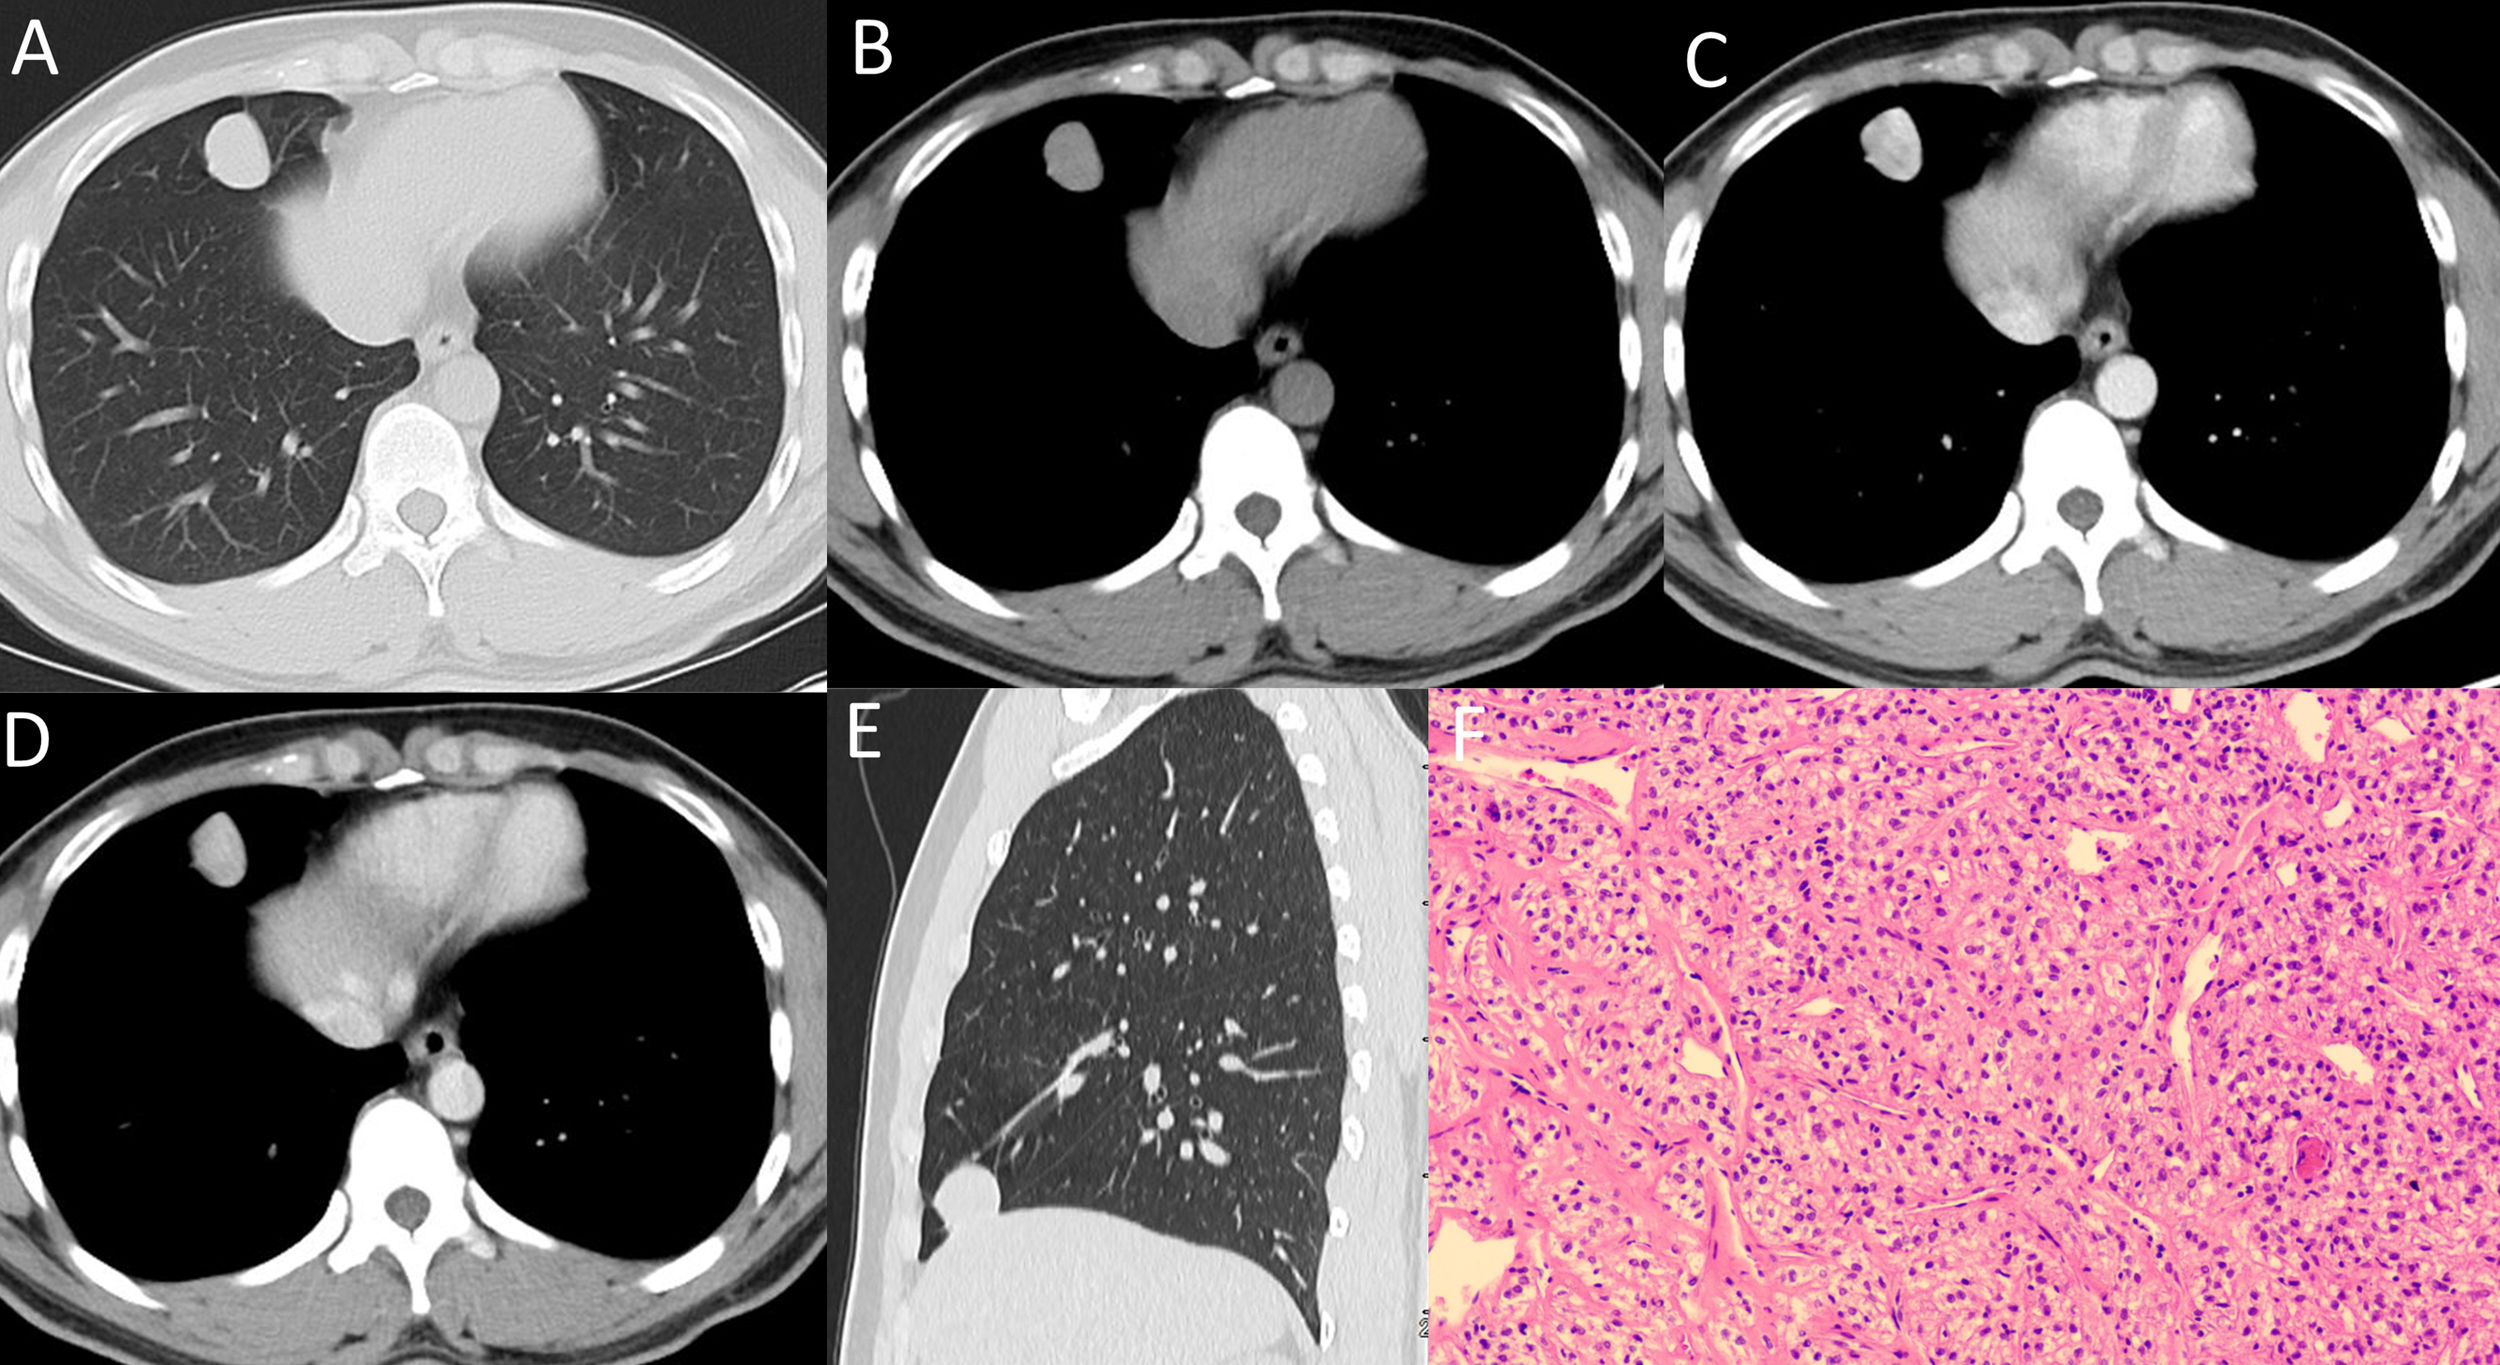

Pulmonary perivascular epithelioid cell tumor in a 24-year-old male